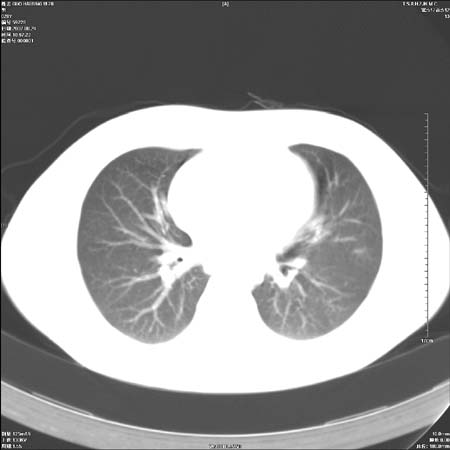

本例倾向周围型肺癌

鉴别:中央型肺癌-肿块那么明显一般合并节段肺不张或阻塞性炎症。

本例肿块边缘外侧可见左上叶各段支气管。

左侧肺门区见一块状病灶可见分叶,纵隔内及左肺门见肿大淋巴结,应该是周围型肺癌而不是中心型肺癌,原因有以下2点,1未见阻塞肺气肿和阻塞性炎症,这么大肿块如果是中心型肺癌就是未分化型或小细胞型肺癌不出现阻塞性肺不张也应该有阻塞炎症或阻塞性肺气肿,2如果是中心型肺癌临床出现最早的症状是咳嗽(此时可无任何异常影象),而此人这么大肿块只有背部隐痛是体检才发现无法解释.

直接下肺癌诊断还太早,病灶较大,估计5cm以上,但阻塞性改变及对临近纵隔及支气管侵犯不明显,密度较均匀,弓旁见一单个淋巴结,需要排除炎症性肿块及腺瘤,平滑肌瘤等。